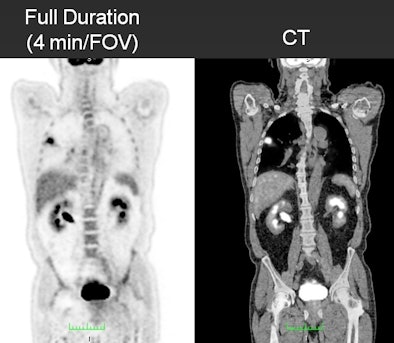

In the study, 20 patients with a mean weight of 165 lb (range, 105-297) received whole-body PET/CT scans (Gemini TF, Philips Healthcare) one hour after injection of 10 mCi of the radiopharmaceutical. Fixed image acquisition durations were set at four minutes, two minutes, and one minute per field-of-view (FOV).

Two reviewers evaluated 115 lesion sites to determine PET/CT's accuracy, with the full duration of four minutes used as the reference standard. Maximum standardized uptake values (SUVs) of primary lesions and noise in the liver were evaluated, along with image quality, which was rated on a scale of 1 (unacceptable) to 5 (excellent).

| The series of images shows image quality over the course of the PET/CT scan in a 178-lb patient. All images courtesy of Adam Alessio, PhD. |

Regarding image quality, the full four-minute study achieved the best image quality, which the two readers rated an average of 4.25. As image acquisition time decreased, so did image quality. Readers rated images from the two-minute duration as 3.8 and from the one-minute duration as 2.9.

"The full-duration studies were deemed to be good to excellent [image] quality; the half-duration were good to very good quality, and the quarter-duration was a little worse," Alessio said. "None of the studies -- even the quarter-duration -- were considered unacceptable. They all had information content and were within the bounds of our two readers for acceptability."

Noise increased 23% at two minutes and 58% for the one-minute study, as measured in a uniform region of the liver, compared with images from the four-minute acquisition time.

Maximum SUVs of primary lesions changed just 1% (± 1%) for the two-minute duration and 3% (± 2%) for the one-minute scan.